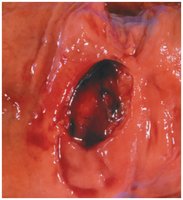

Stomach Ulcer (Peptic Ulcer)

Caused by Helicobacter pylori infection or excessive acid production.

Symptoms: Abdominal pain, nausea, vomiting.

Treatment: Acid-reducing medications and antibiotics.

Ulcerative Colitis

Chronic inflammation and ulceration of the colon mucosa.

Treatment: Medications, surgery, immunosuppressants, dietary management, and bowel rest as needed.